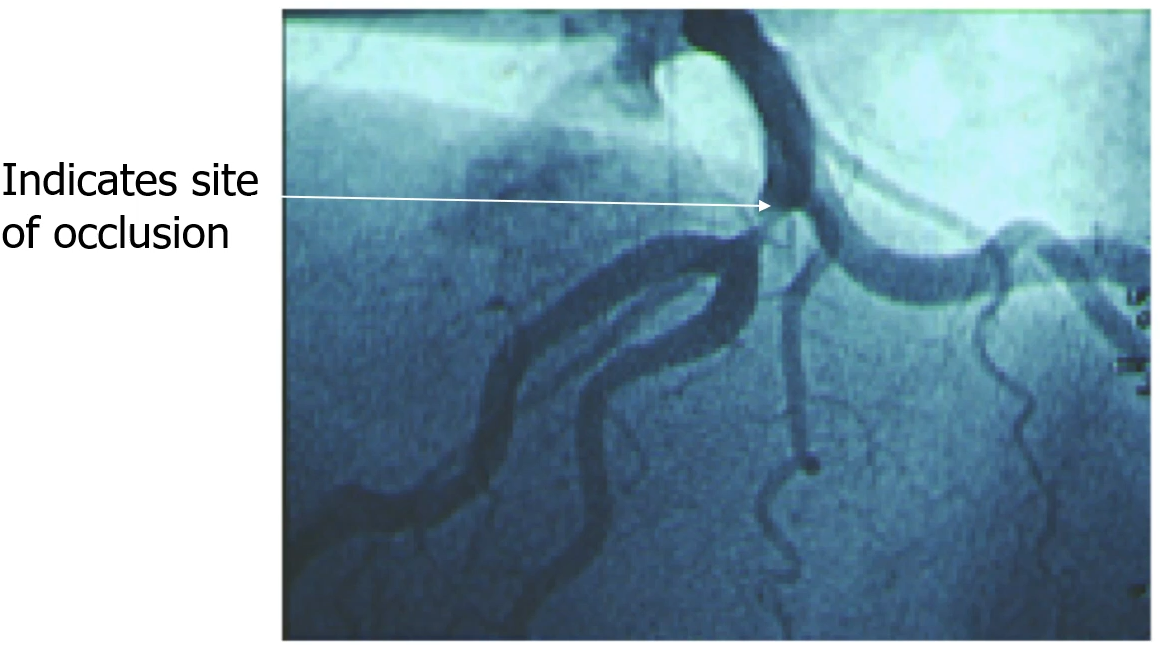

• Angiography:

• indicates site of occlusion